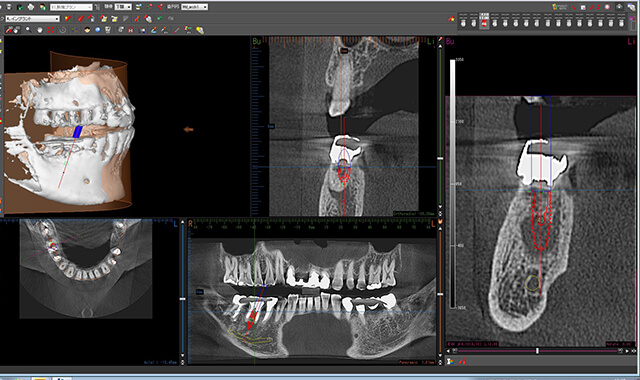

| 治療の説明 | 歯根が破折していた為、診断の結果抜歯が必要となりました。 患者様のご希望で、歯のない部分はインプラントによる治療を行いました。 クラウン(被せ物)は、ジルコニアセラミックスを選択された為、より天然の歯に近い形になりました。 |

| 治療の説明 | 他院で抜歯を行った後、入れ歯を勧められましたが、入れ歯には抵抗があり、他の治療方法を探されていました。 その結果、当院でインプラント治療を希望されました。 患者様のご希望により、歯の欠損部分をインプラントで補い、上部構造(被せ物)にはフルジルコニアセラミックのブリッジを選択されました。 そのため、見た目や噛み心地がより天然歯に近い仕上がりとなりました。 |